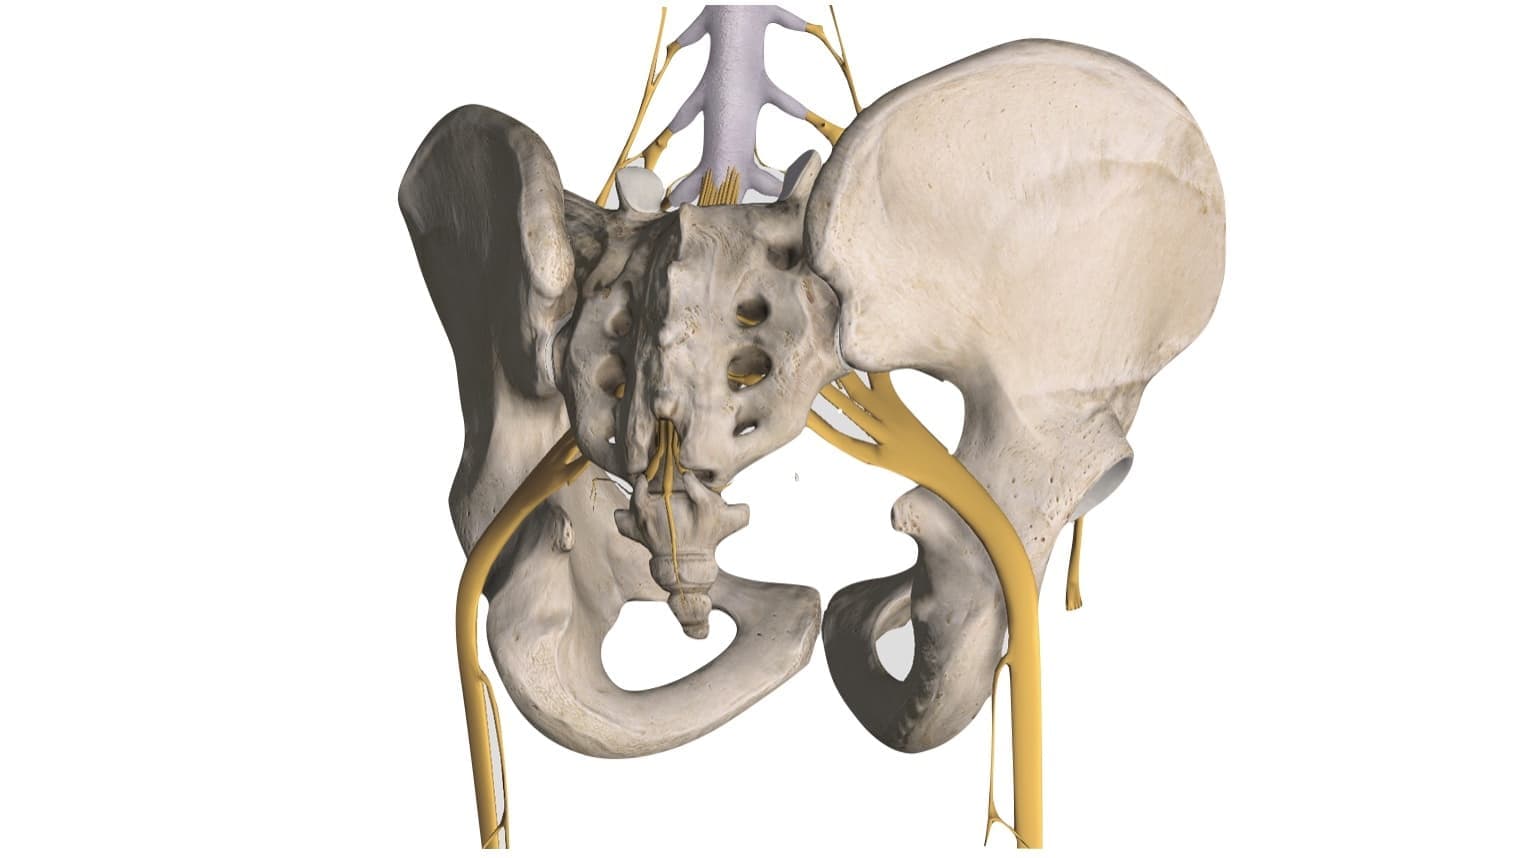

膝関節は骨盤の向き・股関節の角度によって位置が変化するため股関節・腰、骨盤の状態が重要になります。

筋肉と神経

腰部と坐骨神経

また、筋肉に指令を出す神経は「腰~仙骨(骨盤)」にあります。

特に大きい神経である坐骨神経は、仙骨の状態によっては伝達を阻害されることが多いです。

この為、筋肉と神経のどちらか一つでも状態が悪くなると、思い通りの動きが出来なくなりますので、この2つを整えることが重要となります。